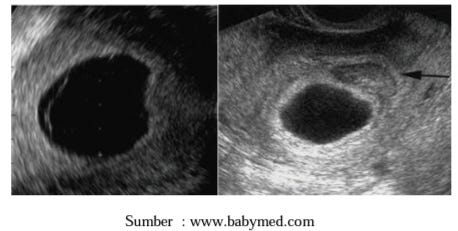

hasil USG BO

hasil USG BO

kantung kehamilan kosong

kantung kehamilan kosong